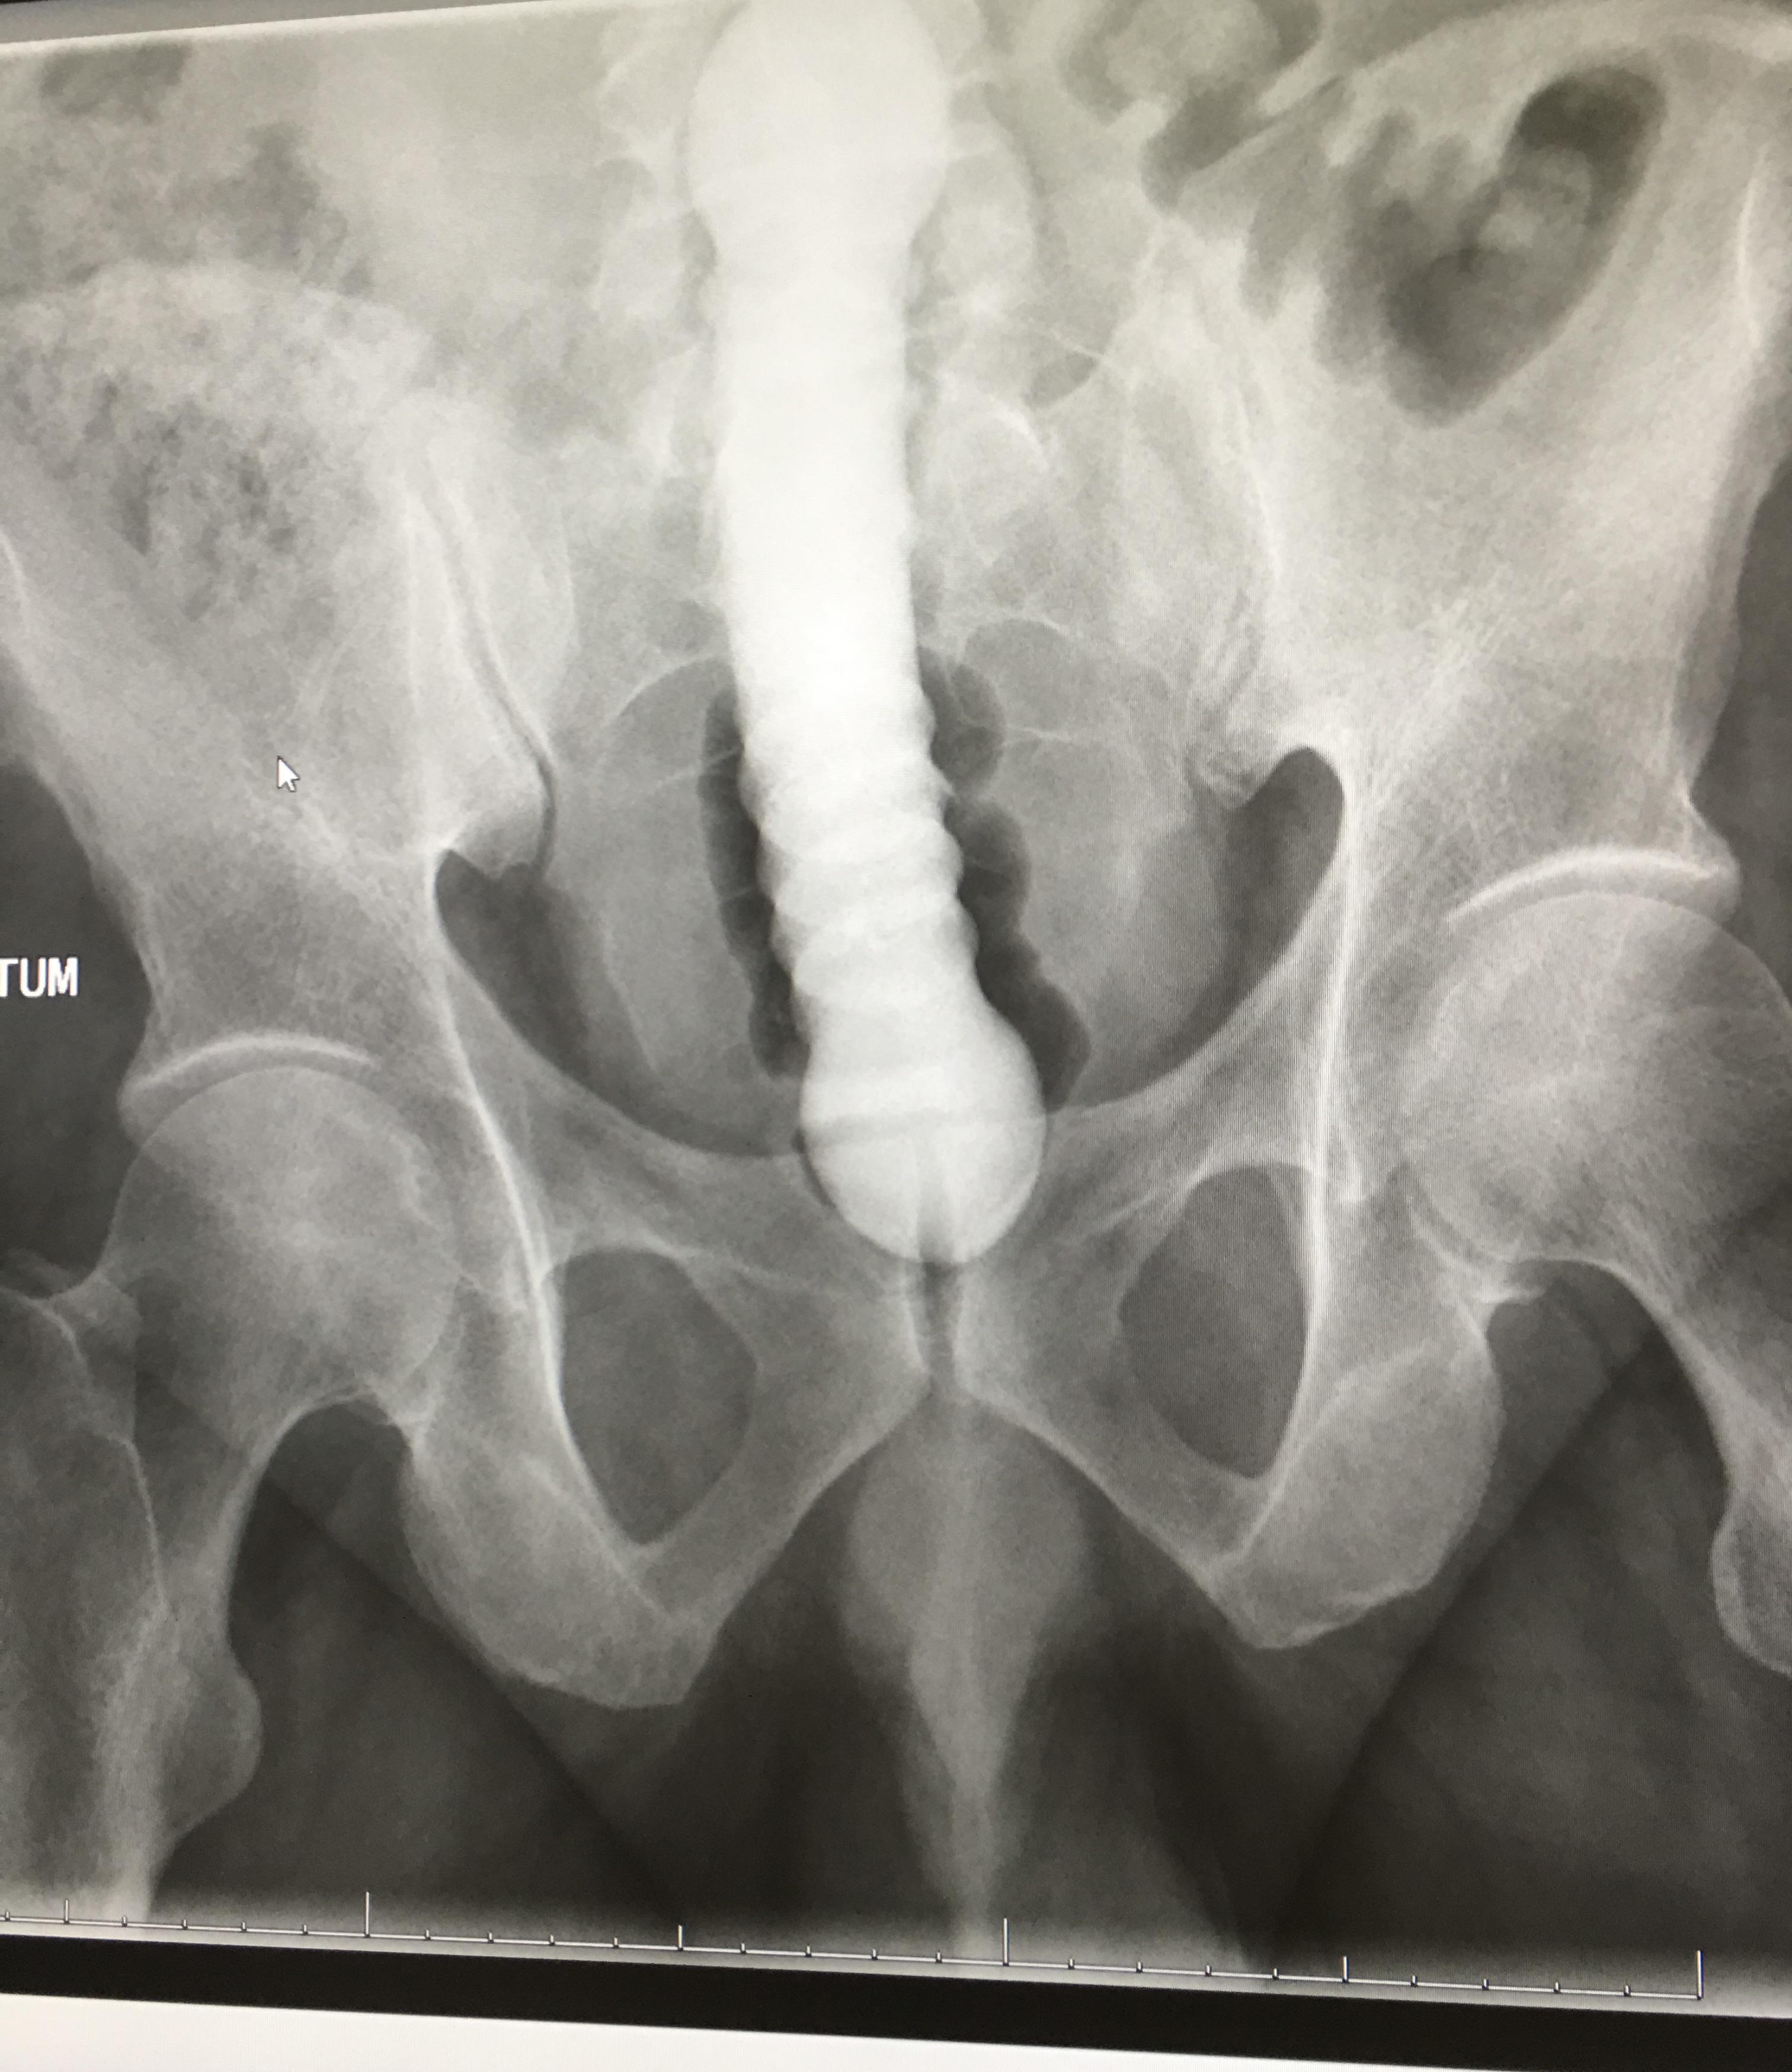

Zur Klarstellung die Zweifel oder einfach nur unwissend sind! Nun mit einer Märchenstunde oder einem Wunschkonzert hat dies nichts zu tun! Falls jemand wissen möchte wo wie und was anbei ein Bild mit den Maaßen kann man käuflich bei den üblichen Chinesen bestellen und bevor nun wieder ohhh China kommt meine Gesundheit nicht die von jemandem der zweifelt ! Und ja dieser geht ganz rein ist eigentlich schon zu kurz !

den trage ich gern zuhause in ruhe, die SB auf dem Bürokloo ganz oldschool mit der Hand! Und die Geilheit zu genießen. Hatte zudem nicht geschrieben das ich mir dort den Dildo einführe 🫣, gut es könnte so verstanden werden! Aber auch das so zu versehen klingt wie ein Märchen !